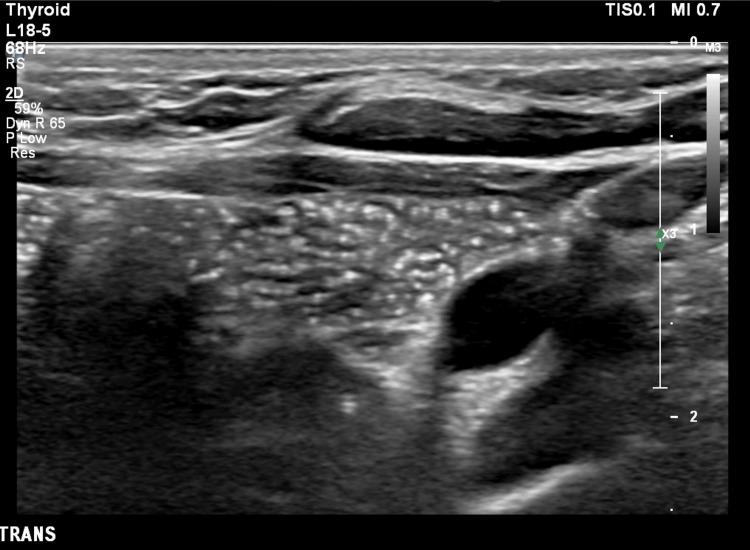

We present a case of conservatively managed intrathyroidal thymic tissue in a 3.5-year-old girl, who had an ultrasound for a midline swelling that was consistent with a dermoid cyst, proven by operative specimen pathology. An incidental finding was that of thymic tissue within the thyroid, the ultrasound characteristics of which enable differentiation from thyroid malignancy, enabling a confident diagnosis of this benign, asymptomatic condition. Thus, rather than proceeding to invasive investigations, detailed ultrasound analysis obviates the need for thyroid biopsy. The features that enable malignancy to be excluded are discussed.

我们报告一例3.5岁女孩的甲状腺内胸腺组织保守治疗病例。该女孩因中线肿胀接受超声检查,最初诊断为皮样囊肿,手术标本病理证实。偶然发现甲状腺内存在胸腺组织,其超声特征有助于与甲状腺恶性肿瘤相鉴别,从而确诊这种良性、无症状的情况。因此,无需进行侵入性检查,详细的超声分析避免了甲状腺活检的必要性。文中讨论了能够排除恶性肿瘤的特征。